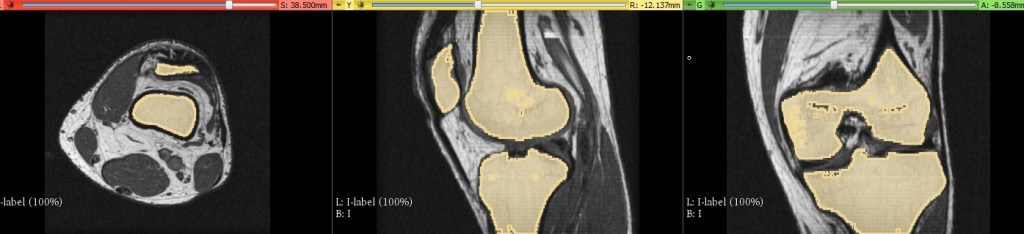

After you have erased everything that is not bone, you should end up with something that looks like what I have below.

Let’s see what our model looks like in three dimensions, you can do this by selecting the create surface button in the segment editor. It will look very rough so you will want to select the smooth function . This should smooth the model making it look considerably better.